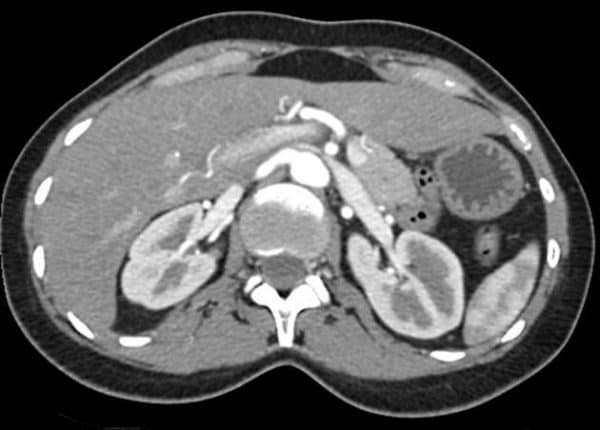

Hội chứng kẹp hạt dẻ

» Thông tin: Nữ giới – 35 tuổi.

» Lâm sàng: Đau mạn sườn trái / Tăng huyết áp.